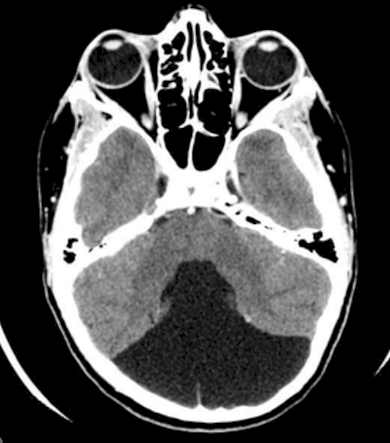

Hydrocephalus

_____ Malformation is associated with bulging fontanelles and macrocephaly.

Dandy-Walker malformation is associated with _____ and spina bifida